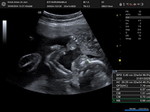

Trimester 3

hi mommys , sorry nak tanya saya first mom, macam mana kita nak tahu + gbs ya ? melalui keputihan kan? kalau keputihan color kuning xberbau xgatal normal ke ? atau kene check jugak ? kita risau sebab baru masuk tm3 ni start keputihan kuning .